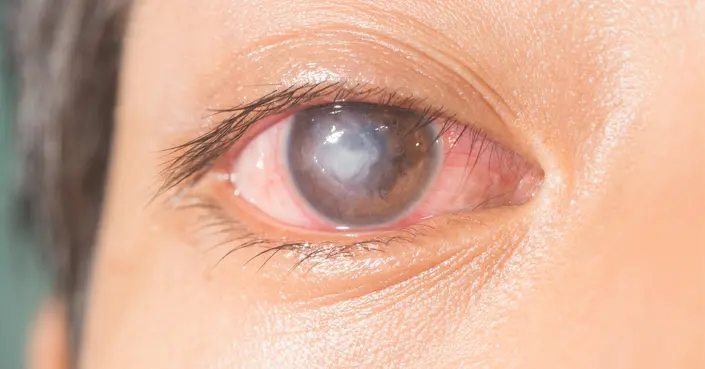

قرحة القرنية، المعروفة طبيًا بـ Corneal ulcer، هي تآكل أو جرح مفتوح يتشكل على الطبقة الخارجية الشفافة من العين، المعروفة باسم القرنية. تُعد هذه الحالة طارئًا طبيًا يتطلب اهتمامًا فوريًا، حيث أن أي تأخير في العلاج قد يؤدي إلى تلف دائم في الرؤية، بل وقد يتسبب في فقدان البصر.

تُظهر قرحة القرنية مجموعة من الأعراض التي يجب الانتباه إليها جيدًا، لأن التعرف المُبكر عليها يُساهم في سرعة العلاج وحماية العين. تشمل أبرز هذه الأعراض ما يلي:

- احمرار واضح ومستمر في العينين.

- رؤية ضبابية أو غير واضحة.

- آلام حادة في العين، خاصة عند التعرض للضوء الساطع (حساسية للضوء).

- ظهور بقعة بيضاء أو رمادية على سطح القرنية.